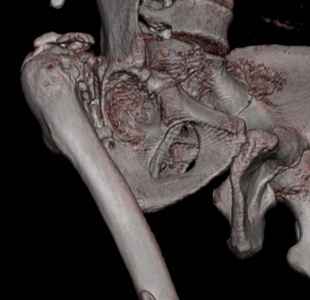

На последнем срезе КТ задний край практически отсутсвует по сравнения со здоровой стороной. Разумеется, что это плоскостное изображение, но головка вывихнулась не только в плоскостную щель захваченную на КТ. Если вы считаете, что удастся установить туда чашку даже низкопрофильную, остается пожелать вам успехов. Но перед этим можно смоделировать установку чашки на скиаграммах КТ.

За пожелание успехов - спасибо, думаю это пригодится, не очень понял про плоскостную щель, специально предоставил срезы на уровне свода - он цел, дефект заднего края ниже, за счет заглубления он будет еще меньше, по данным 3d - должно получиться.

Решение по ВВ придется принимать по месту.... Сумеете "подрыться" и получить хорошее покрытие чашки (+2 винта об-но) - хорошо, если нет -

костная аутопластика из головки.